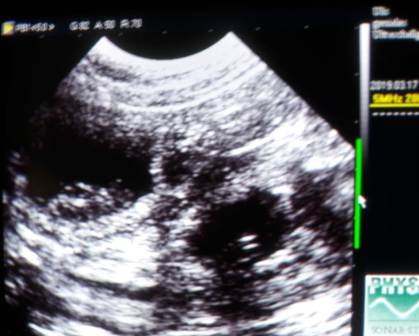

Ich konnte mich nicht zurückhalten und musste heute noch einmal nachsehen :)

Franzi und ich haben viele Fruchtblasen, muntere Babys und schlagende Herzchen gesehen!

Zählen war unmöglich, wie ihr auf dem dritten Bild sehen könnt,

haben sich manchmal an einem Platz fünf Fruchtblasen geöffnet :O

Oft lagen zwei dicht nebeneinander, wie auf dem letzten..

Wir sind sehr gespannt!!!